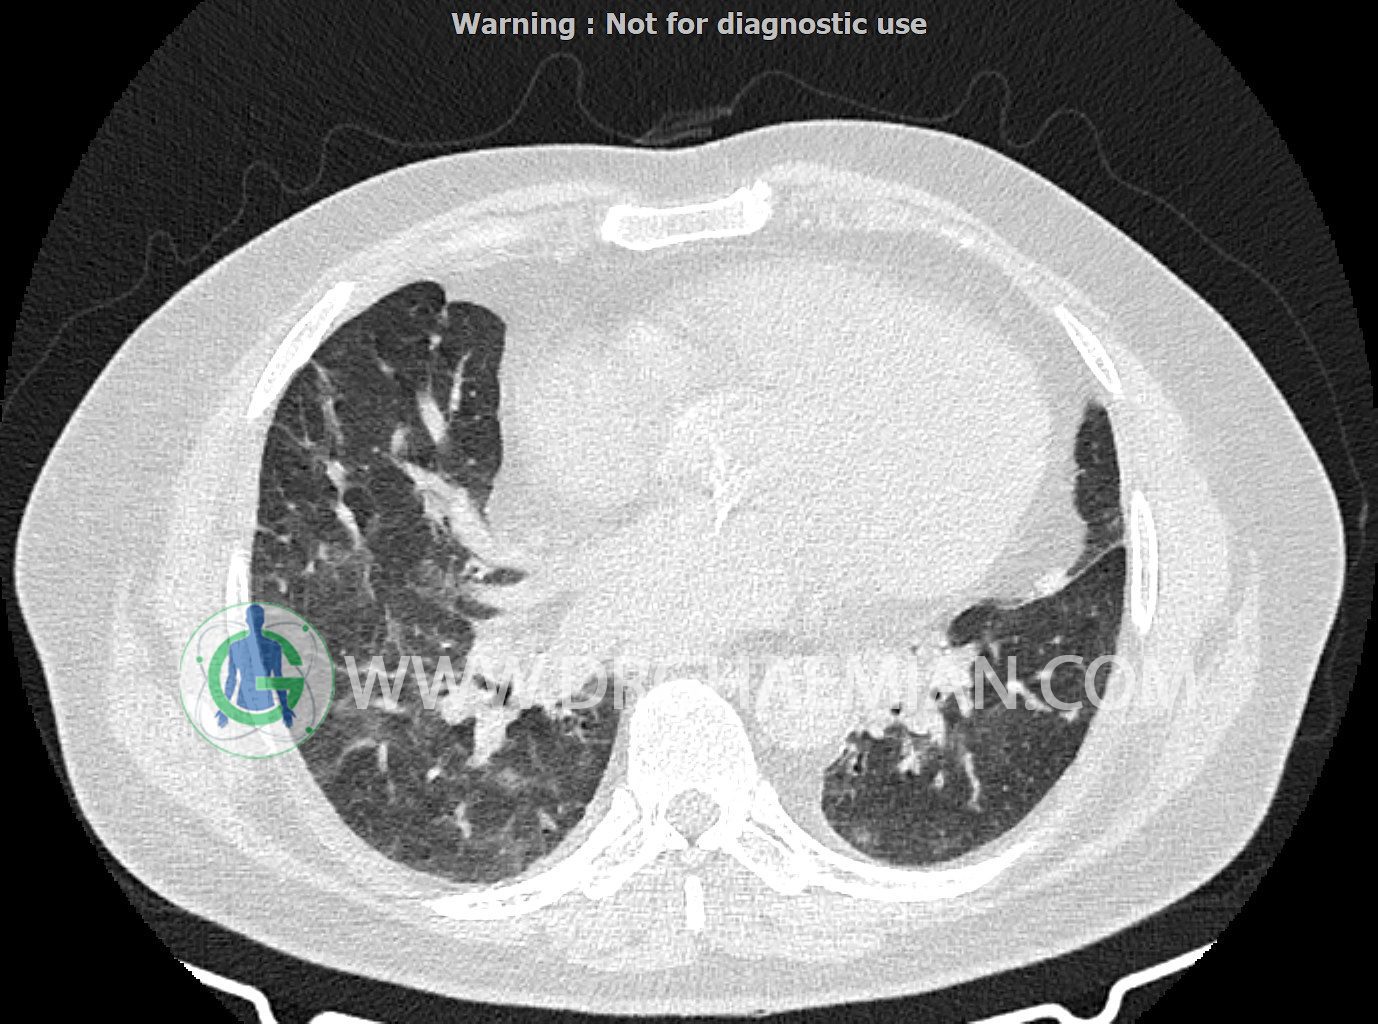

سی تی اسکن ریه یک روش تصویربرداری است که با استفاده از تشعشعات تصاویر عرضی مقطعی از ریه و بالا تنه ایجاد می کند. در این کیس کاردیومگالی،باندهای آتلکتازی و فیبروتیک پراکنده،کدورت های گراند گلاس،زمینه ی ادم قلبی (مراحل اولیه)،مشهده میشود.

در سی تی اسکن اسپیرال ریه ها و مدیاستن بدون کنتراست وریدی (مولتی دیدکتور 16 با مقاطع ظریف و بازسازی کرونال):

باندهای آتلکتازی و فیبروتیک پراکنده در دو طرف

smooth septal thickening در لوب فوقانی ریه ها

peribronchial wall-thickening و عروق prominant در هیلوم دو طرف و کدورت های گراند گلاس دو طرفه

مشهود است.

شواهد فوق در درجه اول می تواند در زمینه ی ادم قلبی (مراحل اولیه) باشد.